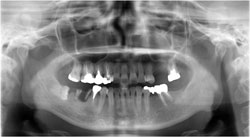

施術から3ヶ月後。インプラントには上部構造(歯の部分)を装着し、

縦に再植した親知らずには、被せ物を装着しました。これで何でも噛めるようになります。